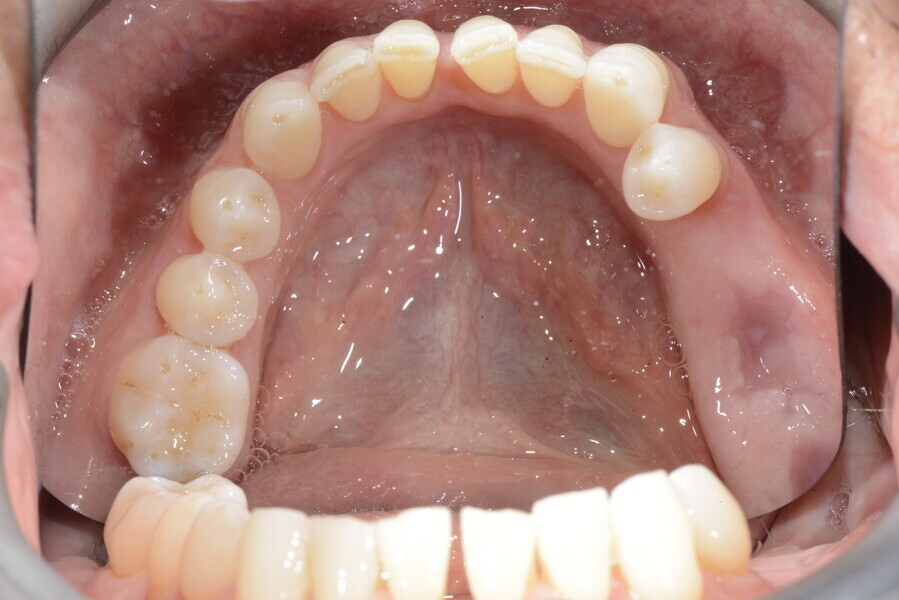

The 58-year-old patient wished to improve his oral aesthetics and function, complaining of mobility of the posterior teeth and wear of the anterior teeth. After data collection, a very complex situation was identified (Figs. 11–13):

1. severe periodontitis with poor prognosis of some teeth;

2. anterior crossbite;

3. severe wear mainly of the anterior teeth and compensatory eruption;38

4. atypical swallowing and lower posture of the tongue at rest;

5. masticatory dysfunction during the mastication test; and

6. no significant signs of temporomandibular disorder.

After the first phase of aligner treatment, we had achieved better inter-arch coherence, better maxillary arch expansion, and some space for improving the anterior tooth proportions restoratively (Fig. 19). We then temporarily restored the anterior teeth directly with composite, closing the spaces, improving the tooth proportions and further increasing the maxillary arch expansion (Fig. 20). We used restorative arch expansion to reduce the orthodontic destabilisation of the teeth to achieve the correct inter-arch coherence and retain the teeth in the cortical bone.38 A refinement aligner phase was undertaken to improve the final alignment of the gingival zenith and to improve the inter-arch coherence (Fig. 21). The periods of the first orthodontic phase and of the refinement were used to augment the mandibular and maxillary bone and to place the implants (Fig. 22). At the end of the orthodontic treatment, the case was finalised with ceramic veneers in the anterior area and temporary restorations on the implants in the posterior area (Figs. 23–26).